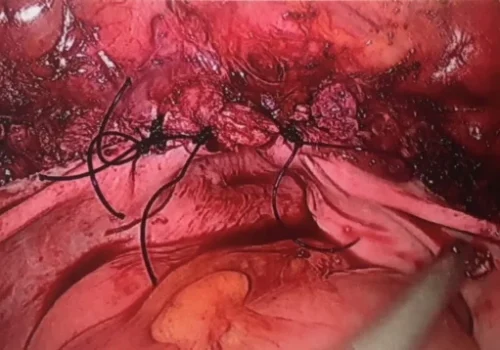

Large Fibroid Uterus - Laparoscopic Hysterectomy

Procedure

She subsequently had a Total Laparoscopic Hysterectomy. The uterus weighed 750g.